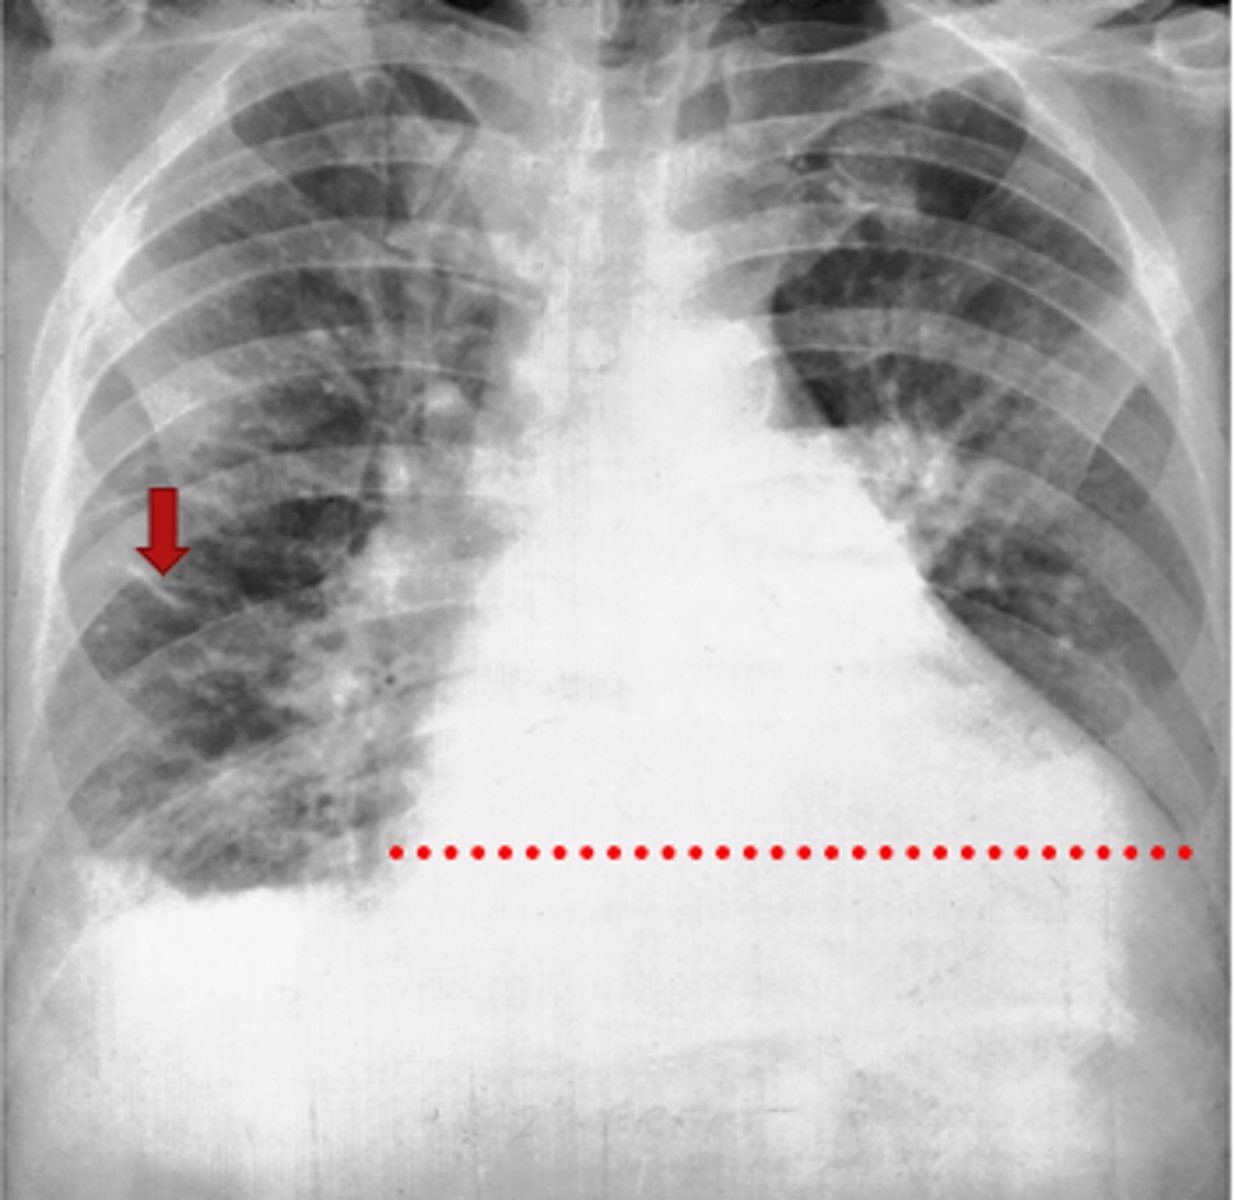

Left lung

Where is the abnormality located in the chest?

Atelectasis

What is the red arrow indicating?

Effusion

What is the likely interpretation?